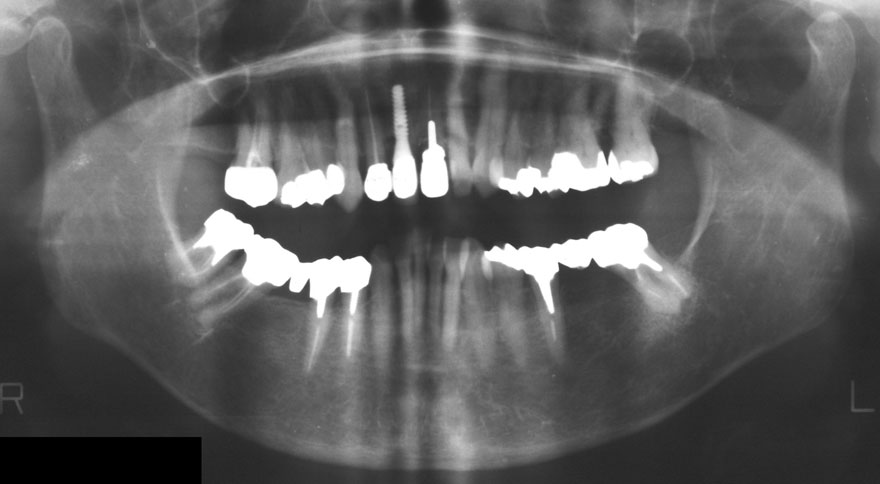

開始年齢 40代

初診時 40歳 女性 平均歯槽骨喪失量:3.14mm

32年後 72歳

平均歯槽骨喪失量:3.22mm

32年間喪失量:-0.08mm

年間喪失速度:-0.002mm

(ケア頻度:1.86ヵ月ごと)